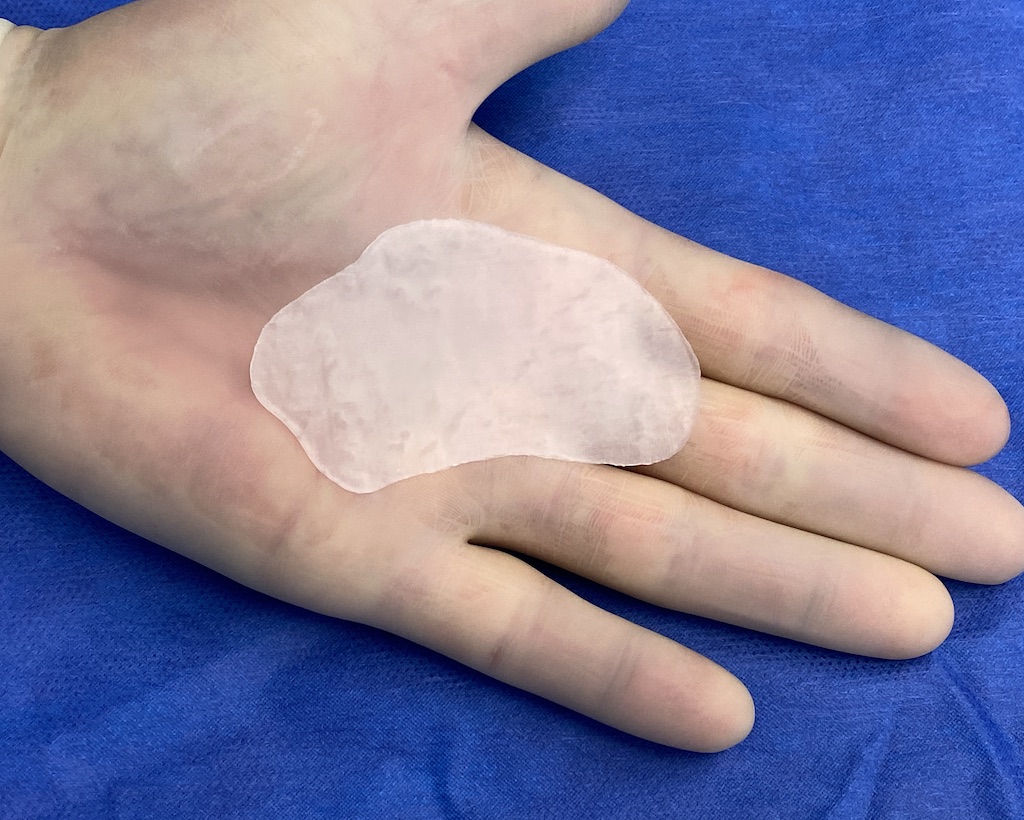

Patient 100

Desire for reshaping of an asymmetric flat back of the head in a shaved head male.

A combined back of the head reshaping procedure was done with a custom skull implant, sagittal ridge reduction and a right temporal muscle reduction.

Desire for reshaping of an asymmetric flat back of the head in a shaved head male.

A combined back of the head reshaping procedure was done with a custom skull implant, sagittal ridge reduction and a right temporal muscle reduction.